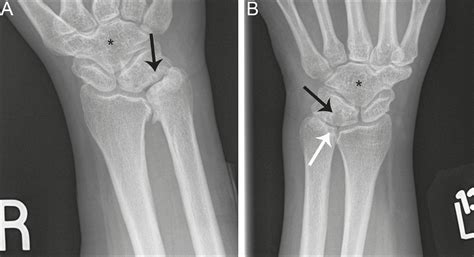

At its core, Ulnar Impaction Syndrome is a degenerative condition characterized by the mechanical abutment of the distal ulna—the bone on the pinky side of your forearm—against the bones in the wrist (specifically the lunate and triquetrum) and the triangular fibrocartilage complex (TFCC). In a healthy wrist, the radius and ulna work in harmony to support the carpal bones. However, if the ulna is relatively longer than the radius, a condition called “ulna positive variance,” it creates a crowded space that leads to repetitive grinding, cartilage wear, and ligament tears.

Imaging is equally vital. Standard X-rays, particularly those taken in a neutral position, help clinicians measure the ulnar variance. In more complex cases, an MRI is ordered to evaluate the extent of TFCC damage, cartilage wear on the lunate, or subchondral bone edema, which is the "bruising" of the bone caused by persistent impaction.